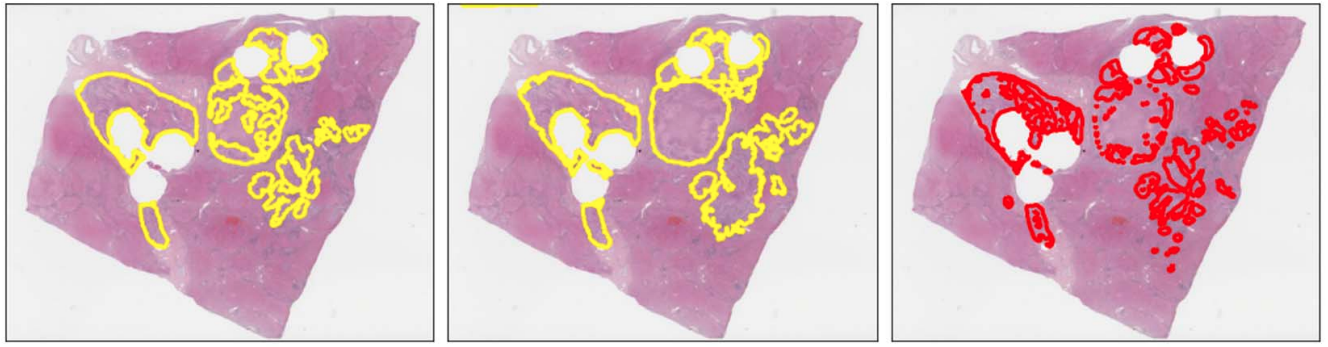

Tools in Digital Pathology

tumor

non tumor

Can we refine these automatically?

false positives

false negatives

• Training on a single slide

necrotic tumor

viable tumor

non-tumor

Manual coarse annotation

Computational refinement

Ground truth